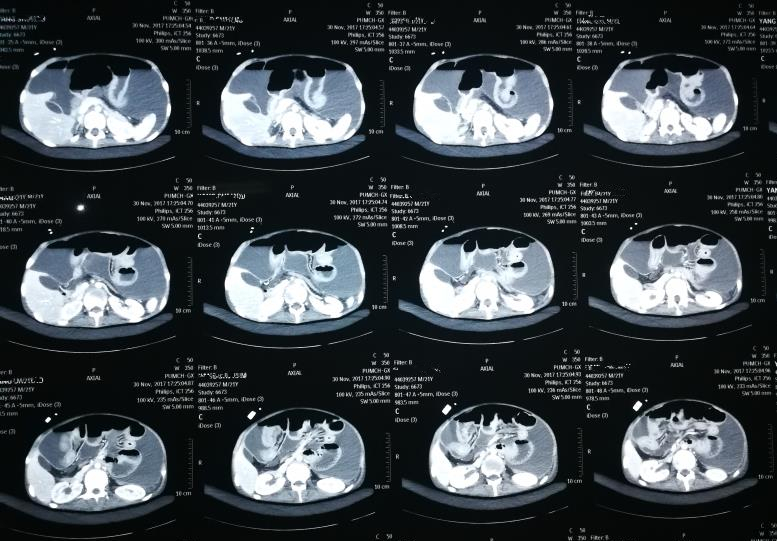

CT影像可见,小浩腹腔内大量积液,胸腔内感染非常严重

当时正在院外开会的王峰以最快速度赶回医院,检查后发现小浩感染突然加重,因感染导致膈肌穿孔,腹腔内的脓液进到了胸腔和气管中。小浩被迅疾转入ICU进行气管插管和吸痰,同时进行腹腔脓液的引流。三天后,胃肠外科李元新主任团队为小浩做了艰难的手术,进行了腹腔引流和膈肌修补,术后当日下午因凝血功能差又发生活动性出血,再次进行急诊手术止血。这次术后,小浩的病情才终于稳定下来,“每天都盼着他们来查房,看到他们就觉得救星来了。”小浩的父亲说。